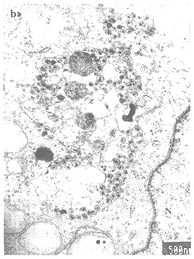

本研究中,偶尔也可在HIV-1 SH01感染的MT4细胞的胞浆空泡内见到HIV颗粒(图2,a),并且在感染7天或持续感染的MT4细胞中均能见到。在有的空泡内,HIV颗粒还相当多见,且形态十分典型,不过除HIV颗粒外,还有细胞碎片和溶酶体结构(图2,b)。可见,此类空泡实际上是HIV的吞噬泡。在HIV-1持续感染的MT4转化细胞中,所见的一HIV吞噬泡位于细胞膜附近,可能是通过吞饮作用刚形成不久的吞饮泡(图2,c)。

图2 (a)在HIV-1 SH01感染7天的MT4细胞中,一胞浆空泡内可见HIV颗粒和细胞碎片。(b)在同一标本的另一空泡中,存在大量的HIV颗粒,核心颗粒的锥形特征明显,同时溶酶体和细胞碎片亦清晰可见。(c)在HIV-1 SH01持续感染的MT4转化细胞中,一已摄入HIV颗粒的空泡位于细胞膜附近,可能是刚形成不久的吞饮泡。

Figure 2 (a) HIV particles and cell debris were found in a cytoplasmic vacuole in MT4 cells infected with HIV-1 SH01 at 7th day. (b) In the same HIV-1 SH01-infected MT4 cells, a lot of typical HIV particles were located in another cytoplasmic vacuole, lysosomes and cell debris could also be seen. (c) An HIV uptaking vacuole was situated at the edge of MT4 cells transformed persistently with HIV-1 SH01 and it is supposed that HIV particles might be engulfed by way of endocytosis.

HIV除了最常见的以芽生的方式释放至细胞外的成熟过程外,根据宿主细胞的不同,亦可出芽至胞浆空泡内[2,6-13]。HIV-1单核一巨噬细胞敏感株,主要出芽至内质网腔或高尔基体囊腔成为胞浆空泡内病毒[6-9],一般认为这种空泡内的病毒可以逃避机体免疫系统的清除,因而巨噬细胞被认为是人体内HIV的庇护所和储存库[9,17,18]。不过,在一些非巨噬细胞系中有时也能见到类似的情形况[2,10-13]。我们所见的胞浆空泡内的HIV颗粒与上述情况不同,空泡内除了HIV颗粒外,还有细胞碎片和溶酶体,显然,此类HIV空泡很可能是通过吞饮作用从细胞外摄入HIV颗粒后形成的一种吞饮泡,而非扩张的高尔基体囊腔或内质网腔。